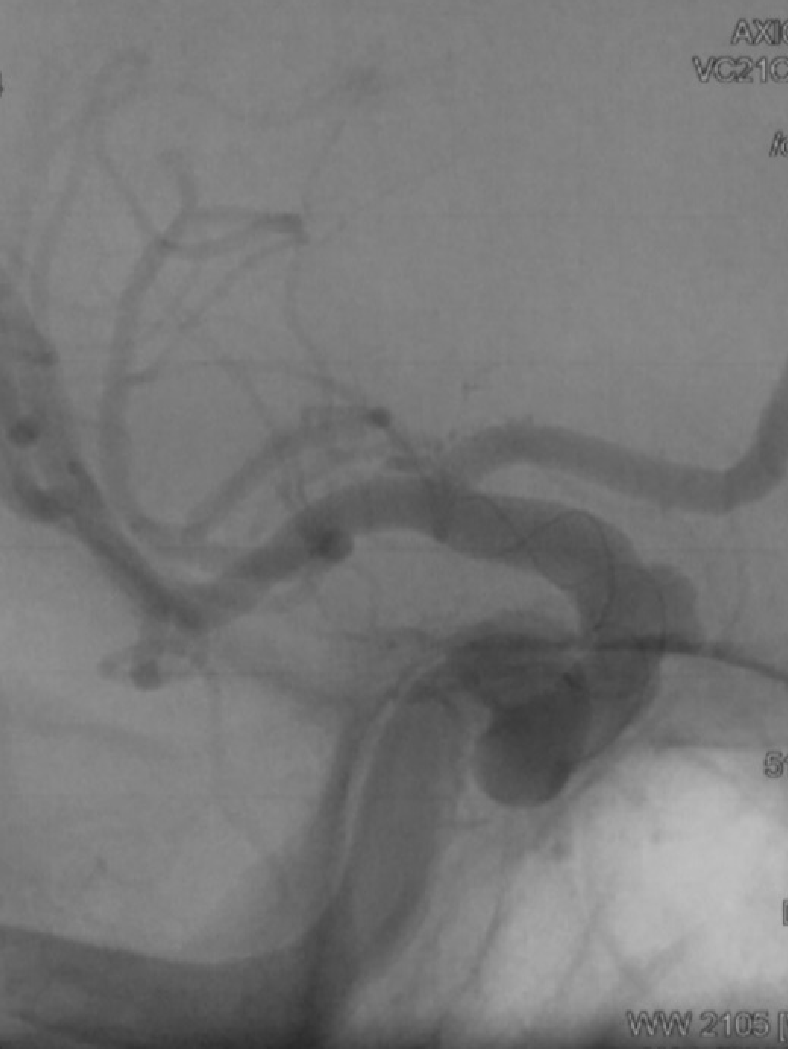

CASE1

后交通动脉瘤,通桥医疗银蛇®DA直接超选,到达海绵窦段;双微导管栓塞,银蛇DA提供稳定支撑;在双微导管调整张力时,通桥医疗银蛇®DA头端并没有移位,最后放了支架,通桥医疗银蛇®DA仍能稳定支撑。术后血管形态良好,无痉挛发生。